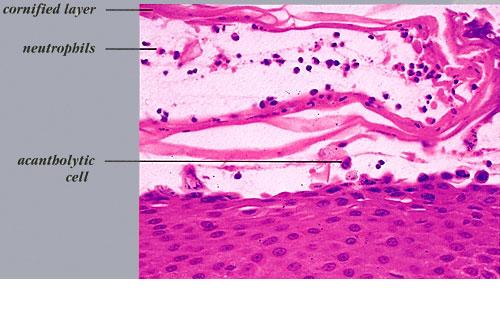

Staphylococcal scalded skin syndrome = متلازمة الجلد المسموط بالعنقوديات